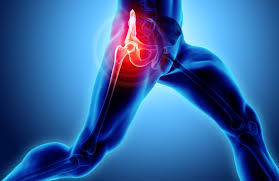

(1) 통증 양상

사타구니 통증

고관절 통증은 주로 사타구니 부위에서 시작되며, 허벅지 앞쪽이나 엉덩이로 방사될 수 있습니다.